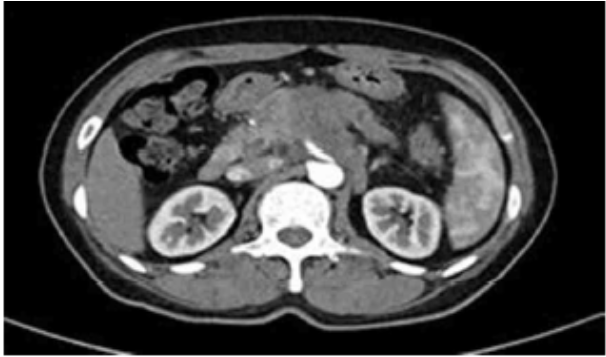

65세 남자가 1주 전부터 배꼽 주위에서 딱딱한 덩이가 만져진다고 병원에 왔다. 1개월간 몸무게가 70 kg에서 65 kg으로 줄었다고 한다. 20갑•년 흡연자이다. 25년간 소주 1병씩을 주 3~4회 마신다고 한다. 혈압 110/70 mmHg, 맥박 92회/분, 호흡 18회/분, 체온 36.6℃이다. 배에 가벼운 압통이 있고 반동압통은 없다. 혈액검사 결과는 다음과 같다. 복부 컴퓨터단층촬영 사진이다. 진단은?

CT: Hypoattenuating mass in pancreatic body

Imp: 췌장암(pancreatic cancer)

20갑년의 흡연력이 있는 환자에게서 복부 덩이 및 급격한 체중감소 소견과 함께, 복부 CT상 pancreatic mass가 확인되므로 췌장암이 가장 의심된다.

• 원인 확인을 위해 시행한 복부 CT상 pancreas body 부위에서 hypoattenuating mass가 관찰된다.

• 환자의 임상증상, 흡연력, 복부CT 소견을 종합할 때 췌장암(pancreatic cacner)이 가장 의심된다.